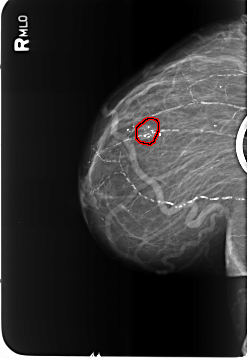

B_3481_1.RIGHT_CC

RIGHT_CC LINES 5808 PIXELS_PER_LINE 3888 BITS_PER_PIXEL 12 RESOLUTION 50 OVERLAY

FILE: B_3481_1.RIGHT_CC.OVERLAY

TOTAL_ABNORMALITIES 1

ABNORMALITY 1

LESION_TYPE CALCIFICATION TYPE COARSE-PLEOMORPHIC DISTRIBUTION CLUSTERED

ASSESSMENT 2

SUBTLETY 5

PATHOLOGY BENIGN

TOTAL_OUTLINES 1

BOUNDARY